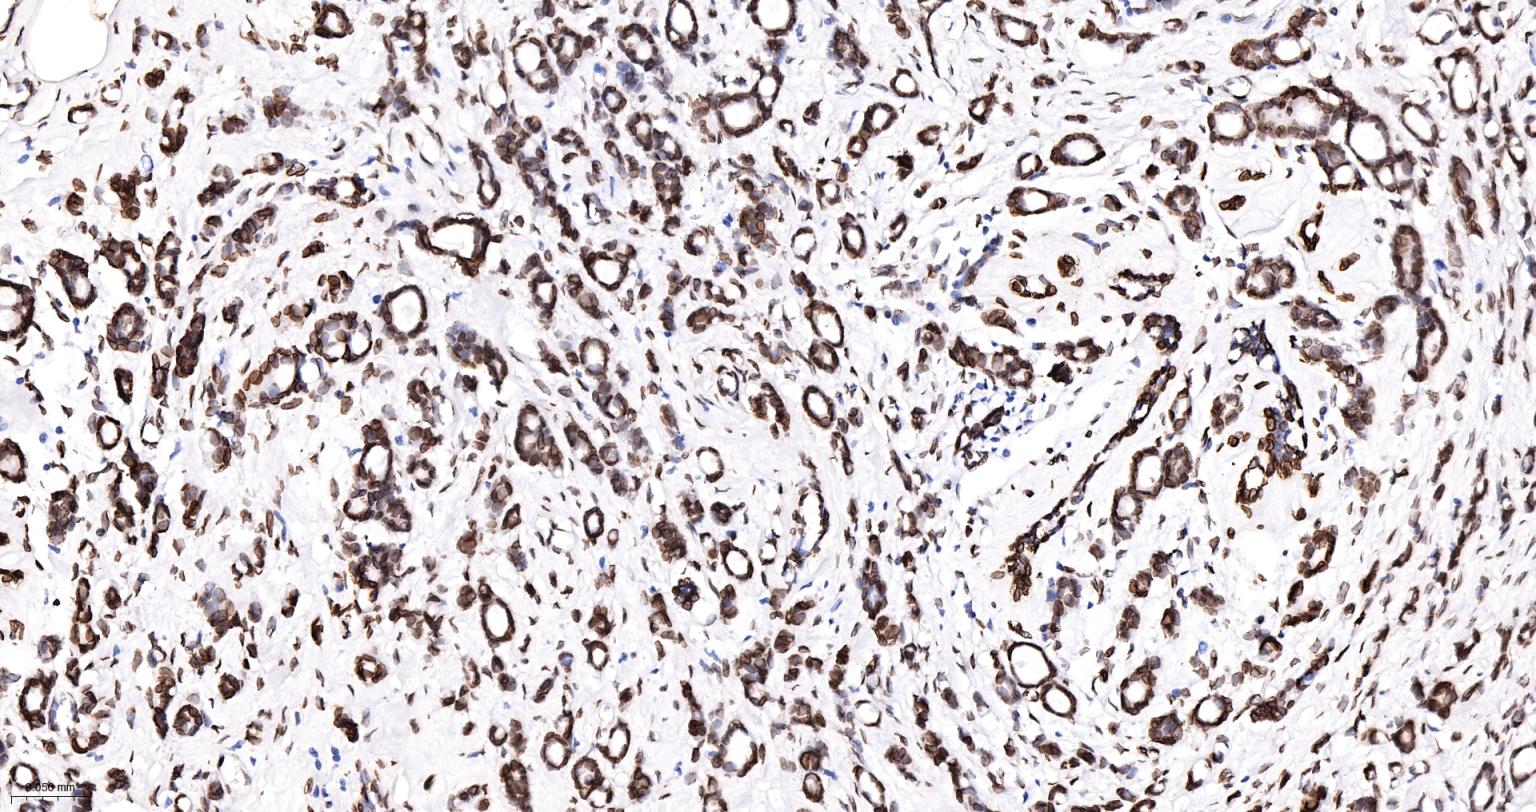

Paraformaldehyde-fixed, paraffin embedded Human Breast Cancer; Antigen retrieval by boiling in sodium citrate buffer (pH6.0) for 15 min; The section was incubated with Lamin A/C Monoclonal Antibody, Unconjugated (bsm-62886R) at 1:400 overnight at 4°C, followed by conjugation to the bs-0295G-HRP and DAB (C-0010) staining.